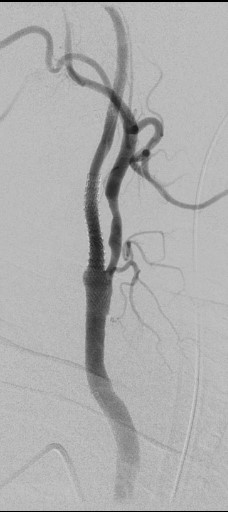

Выполнена реканализация проводником правой ВСА с применением проксимальной защиты. При помощи микрокатетера выполнена тромбоэкстракция из правой ВСА стент- ретривером 6-20(Рис 5.). Удалены тромботические массы. В клиноидном отделе (С 3 сегменте) правой ВСА атеросклеротическая бляшка со стенозом 95%, СМА окклюзирована.(Рис 6,7.) Тромбоэкстракция из СМА справа с полной реканализацией.( mTICI3) (Рис 8,9.) Далее выполнено стентирование правой ВСА стентом 7,0-40мм., с дальнейшей постдилатацией баллоном 6,0-20мм. (Рис 10.) После предилатации баллоном 2,0-10(результат:остататочный стеноз70%) , выполнено стентиование клиноидного отдела правой ВСА баллонорасширяемым стентом 3,0-18мм., постдилатация 3,5-16мм. (Рис 8и9).

рис. 5 рис. 6

рис. 7 рис. 8

рис. 9 рис. 10